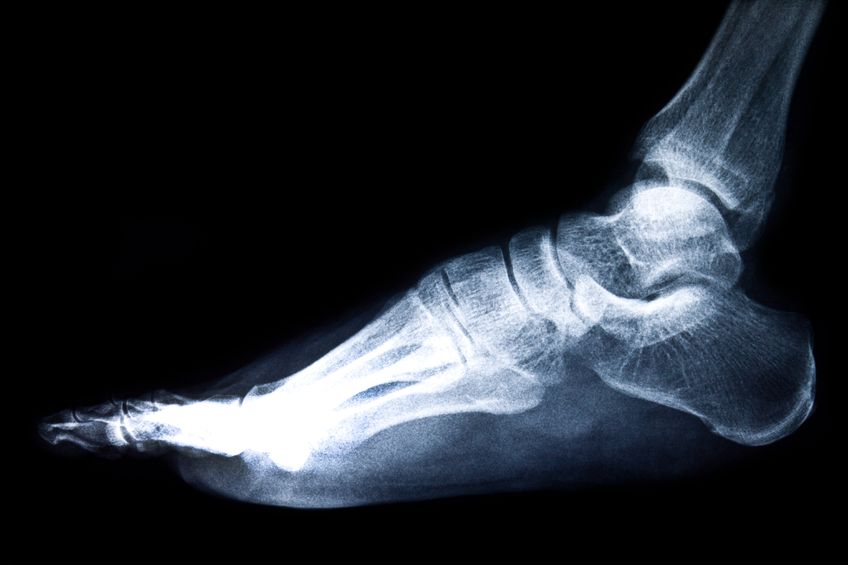

A turf toe is a sprain of the main joint of the big toe. The injury occurs when the toe is bent up into hyperextension. These types of sprains became prevalent in American football players after artificial turf was introduced, which led to the name turf toe. Artificial turf is much harder than natural turf […]